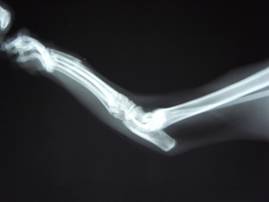

今回は相談の上、ギブス固定を行うことになりました。

ギブスを巻いた様子。上からオレンジの包帯で保護してあります。